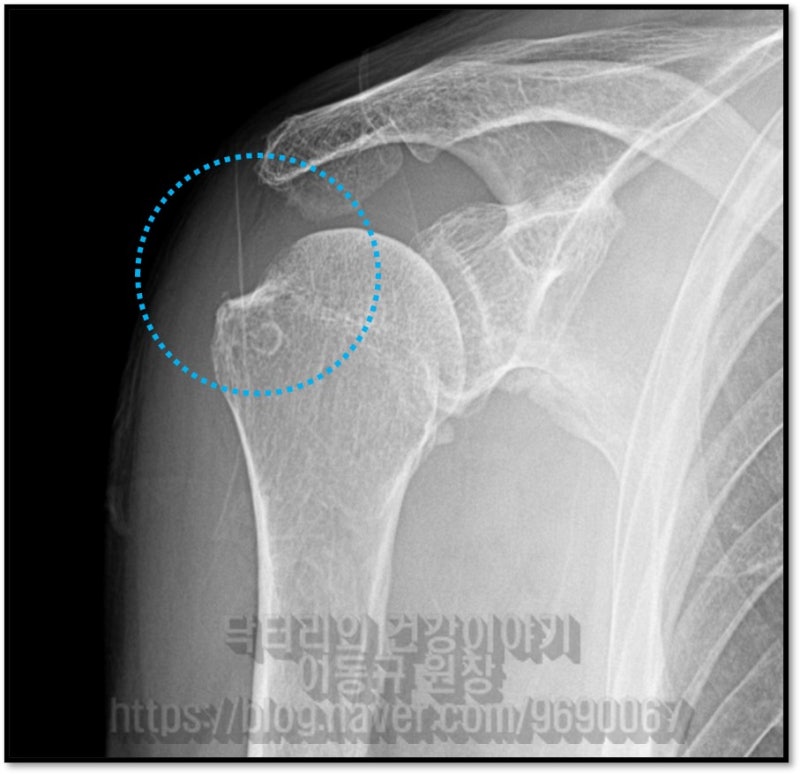

등등 말씀을 하십니다. 왜 정확히 진단을 하지 않고 왜 제대로 된 치료를 하지 않는 걸까요? 오늘 말씀드릴 케이스는 83세 환자분 입니다. 환자분은 어깨가 아파서 동네 병원에 갔는데 염증 있다고 아프면 주사맞고 좀 괜찮다가 또 아프고....그럼 또 주사 맞고... 이런 것을 3년 동안 해 왔다고 하였습니다. 그런데 이제는 주사 맞아도 효과도 없고 점점 더 아파지면서 가동범위 제한까지 와서 일상생활이 힘들고 밤에 아파서 잠을 못잔다고 하시면서 제발 고쳐달라고 하시면서 저한테 오셨습니다. 검사를 진행하였습니다.

환자분이 나이가 83세 이시지만 치료의 의지가 있고 건강상태도 좋았고 수술적 치료를 하였습니다.